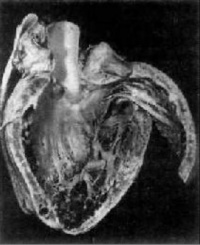

克山病的主要病变是心肌实质的变性、

坏死和纤维化交织在一起心脏呈肌原性普遍扩张,心壁通常不增厚。20%的患者可见附壁血栓及肺、脑、肾、末梢血管的栓塞。光镜可见心肌变性和坏死。心肌变形呈弥漫性,坏死呈灶状分布。病变通常以左心室室间隔部为重,右心室较轻。点镜主要表现为线粒性肿胀、增生和嵴及肌原纤维破坏。